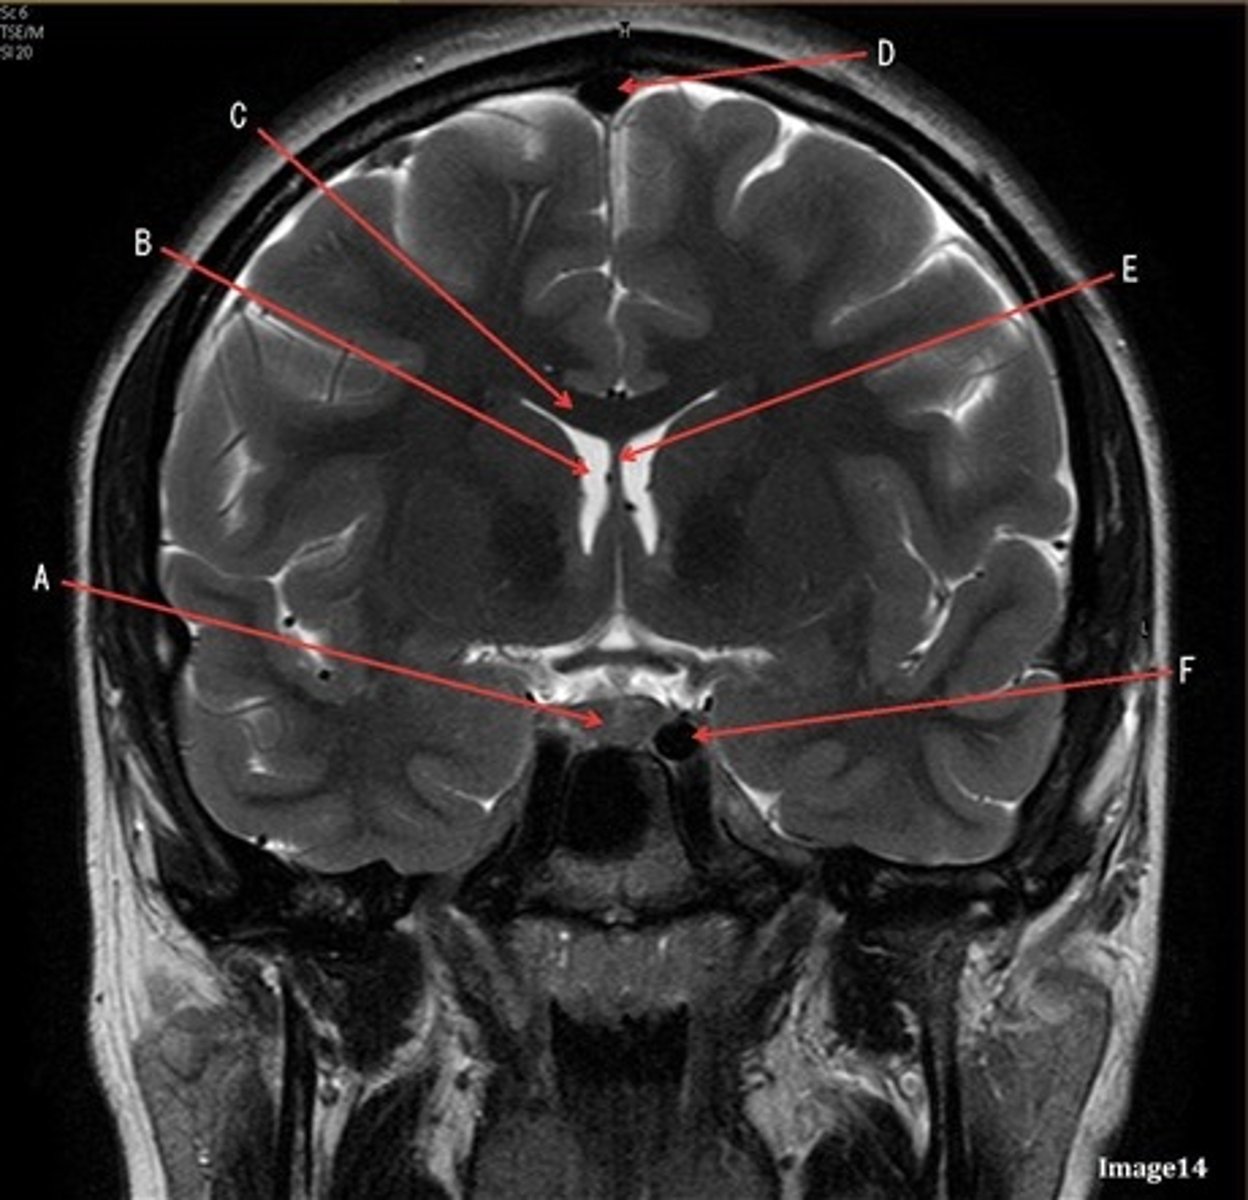

A

lateral ventricle

B

corpus callosum

C

thalamus

D- separates what

tentorium cerebelli- cerebrum (occipital and temporal lobes) from brainstem and cerebellum

E

fourth ventricle

F

medulla oblongata

caudate nucleus

third ventricle

D

lentiform nucleus

frontal sinus